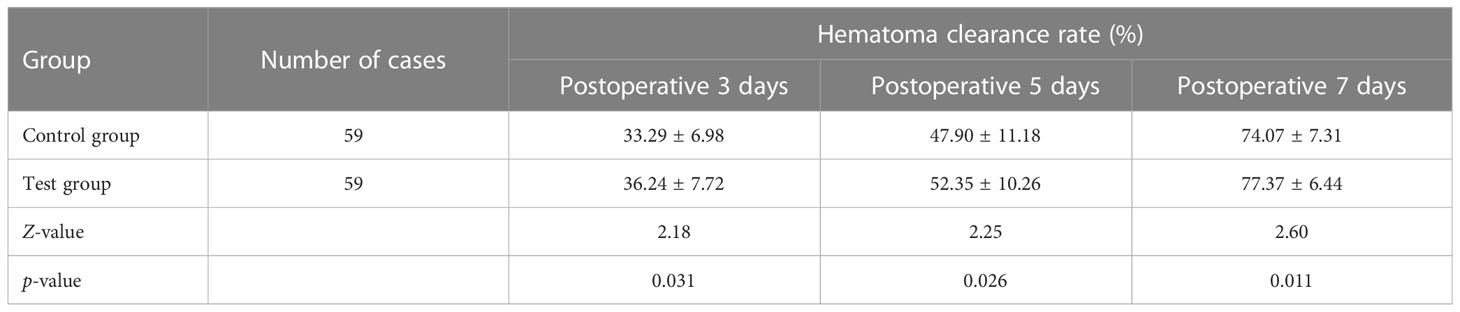

3.1 Comparison of hematoma clearance rate between the two groups

The hematoma clearance rates of the test group at 3, 5, and 7 days after surgery were significantly higher (p < 0.05) than those of the control group (Table 1). This result shows that the hematoma and pressure on the brain were significantly reduced at an early stage in the experimental group, with the restoration of the local blood supply to the brain tissue.

Results: The hematoma clearance rates of the group using 3D laser combined with C-arm CT at 3, 5, and 7 days after surgery were significantly higher than those of the control group, and the difference was statistically significant (p < 0.05). One month postoperatively, the daily living ability (ADL) grading and recovery of the patients in the test group was significantly better than those of the control group (p < 0.05), but there was no statistically significant difference in ADL 3 and 6 months after surgery (p > 0.05).